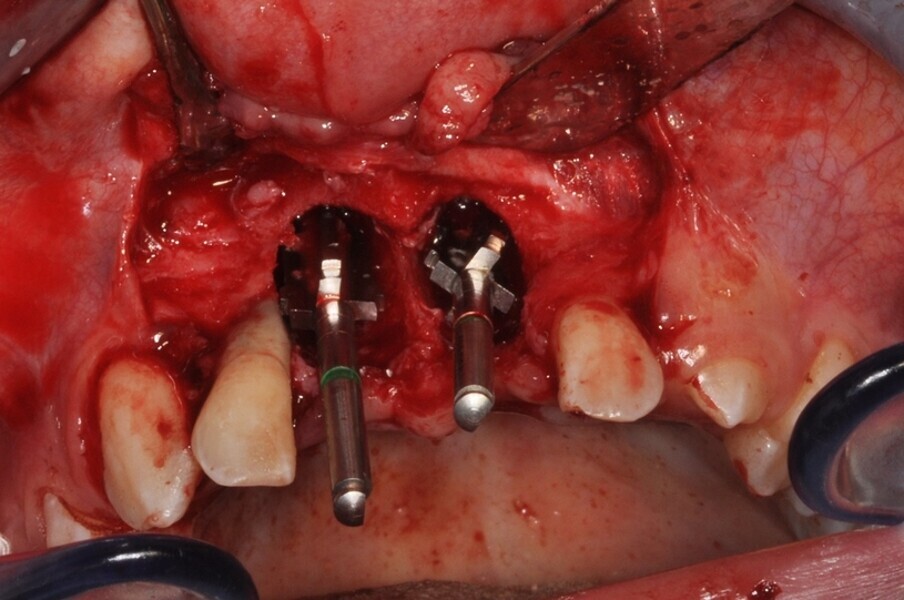

Ryc. 9_Miejsce biorcze po wytworzeniu łoża.